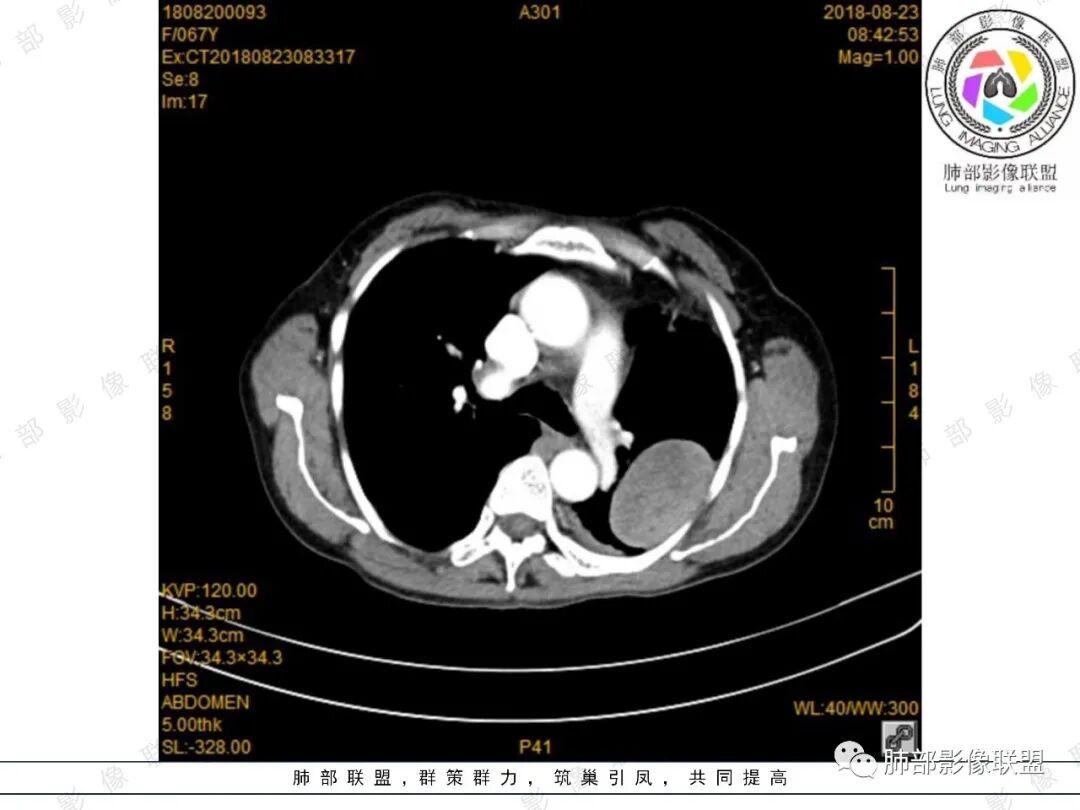

月亮圆了!:左肺上叶胸膜下肿块,宽基底与胸膜相连,边缘清晰,局部肺组织受压,支气管显示不佳,平扫密度不均匀,增强后,可见轻度不均匀强化,纵隔光滑,无分叶,无毛刺,周围组织无牵拉,收缩,内部有不均匀低密度,脾脏明显肿大,脾内多发类圆形低密度影,增强后,轻度强化,有便血,考虑可能:1:淋巴瘤2:脾梗死。

杨丽:老年女性,宽基底及胸膜掀起,考虑肺外病灶,供血动脉看不太不清,中等不均匀强化,首选sft;脾大,较均匀强化肿块,一元论考虑转移机会大,也不好除外二元论,淋巴瘤?

King:很有意思,能想到髓外造血的老师水平高。首先定位胸膜可能大,倾向良性,渐进强化,脾脏多发占位,渐进延迟强化,两者强化有类似之处,倾向一元论。病灶边缘斑点钙化,淋巴瘤少有。消化道肿瘤转移,胸膜孤立转移少有。恶性孤纤伴脾脏转移,也少。贫血,髓外造血,可以,但胸膜相对少见。副脾,少见部位,强化度差点。总之一元论的话像个少见病变,难以确定,就排个序吧。一元:髓外造血>副脾>淋巴瘤。二元:孤纤+血管瘤/错构瘤.

joyzhy:脾脏占位增大,特点延迟期强化和脾脏一致,考虑血管瘤。胸部占位,考虑肺外,鞘瘤或髓外造血。

4、密度、信号及骨骼情况:由于髓外造血组织呈缓慢的代偿性增生,因而病灶边缘光滑。又因血供较好,病变无囊变和钙化。EMH由不同阶段的造血细胞组成,平扫呈等或稍高密度,增强扫描处于造血活跃期的肿块呈中度~明显强化,处于缓解期的肿块,由于脂肪变性无明显强化。

EMH影像表现结合其临床资料,一般诊断不难。患者有明确的慢性溶血或慢性造血功能障碍病史,出现全身或局部多发瘤样肿块、密度均匀、增强后中度强化,MRI上“周围脂肪带”征等情况时,应该考虑到EMH的可能。